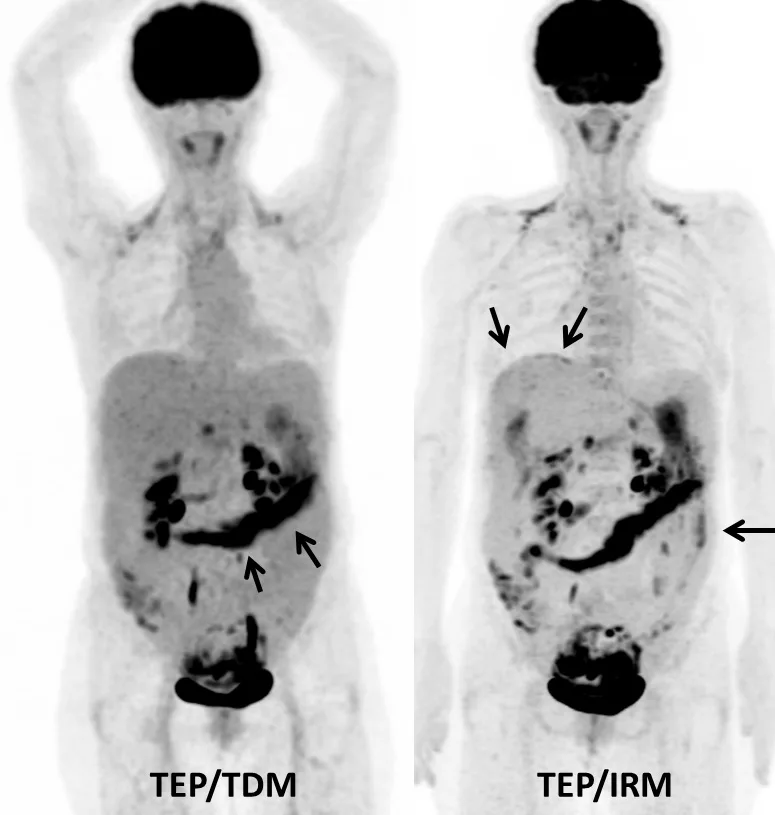

Deuxièmement, c’est la restadification des cancers digestifs, notamment colorectaux. Un bilan comprenant une imagerie thoraco-abdomino-pelvienne composée de TEP, de coupes axiales T2 et de diffusion, complétée par une imagerie abdominale post contraste, peut être réalisée en moins de 45 minutes (Fig. 2). Des acquisitions plus ciblées au niveau du rectum (tumeur en place ou en post thérapeutique), ou du pancréas peuvent aussi compléter l’exploration.

Le TEP/IRM pourrait ainsi être utilisé en remplacement du bilan d’imagerie conventionnel des tumeurs solides qui inclut souvent un TEP/TDM, un scanner abdomino-pelvien et/ou une IRM. Cette approche nous semble prometteuse pour les bilans des récidives des cancers digestifs, des cancers mammaires, ORL et pelviens, et potentiellement pour les bilans initiaux des cancers du rectum et du col de l’utérus.

Amélioration de la confiance ­diagnostique

En couplant l’IRM au TEP, on observe une diminution des faux positifs et des faux négatifs du TEP classiquement observés au cours du TEP/TDM [26]. L’imagerie IRM cérébrale, de la moelle osseuse et hépatique simultanée et combinée au TEP permet d’améliorer la caractérisation de l’hyperfixation de FDG. C’est en particulier dans le domaine de l’imagerie hépatique que le TEP/IRM pourrait s’imposer comme une référence. En effet, les études des dix dernières années ont montré que le TEP au FDG manquait de sensibilité pour la détection des métastases hépatiques, et ceci pour plusieurs raisons : résolution spatiale plus faible qu’en scanner ou en IRM, présence de mouvements respiratoires et digestifs entraînant un flou lésionnel, bruit de fond hépatique pouvant gêner l’individualisation de petites lésions, et faible métabolisme glucidique pour certains types histologiques tumoraux. Les systèmes de détection TEP plus récents, notamment grâce à la technologie de temps de vol et aux possibilités de modéliser la fonction de réponse du détecteur, permettent d’obtenir des images plus contrastées et mieux résolues. Ainsi, les performances des systèmes TEP modernes sont clairement améliorées, particulièrement en termes de sensibilité (Fig. 3a). De plus, la TEP au FDG offre une très bonne spécificité au niveau hépatique, ainsi qu’une bonne valeur prédictive positive. En effet, en dehors de contextes particuliers, tels que les abcès du foie ou les lésions post radiques ou en cas de certains adénomes inflammatoires, il existe peu de faux positifs hépatiques en oncologie digestive. Parallèlement, l’IRM hépatique moderne, incluant l’imagerie de diffusion et éventuellement les produits de contraste hépato spécifiques, constitue aujourd’hui l’examen le plus sensible pour la détection des lésions hépatiques. Cependant, certaines lésions de petite taille peuvent être difficiles à caractériser. Ainsi, l’imagerie simultanée TEP/IRM pourrait devenir un examen performant pour le bilan de lésions hépatiques en combinant la haute spécificité du TEP et la haute sensibilité de l’IRM, notamment en cas de bilan préopératoire (Figs 3b, 4a et 4b).